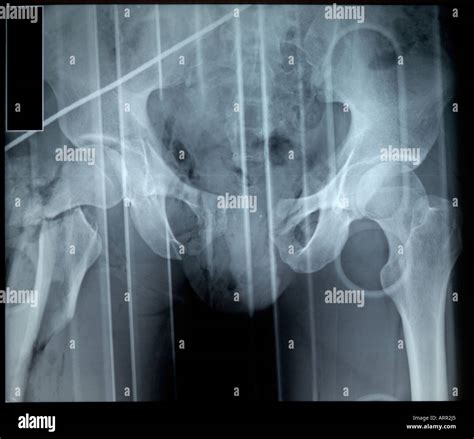

Understanding the Broken Pelvis Open Book Fracture

A broken pelvis open book fracture is a specific type of pelvic injury where the pelvic ring is disrupted, causing the pelvis to widen like an open book. This type of fracture is typically the result of significant force applied to the pelvis, such as in a frontal collision during a car accident. The force causes the pelvic bones to separate at the symphysis pubis, leading to instability and potential internal injuries.

Diagnosing a Broken Pelvis Open Book Fracture

Diagnosing a broken pelvis open book fracture involves a combination of physical examination and imaging tests. The diagnostic process typically includes:

• X-rays to visualize the pelvic bones and identify the fracture.

• CT scans to provide detailed images of the pelvic structure and assess the extent of the injury.